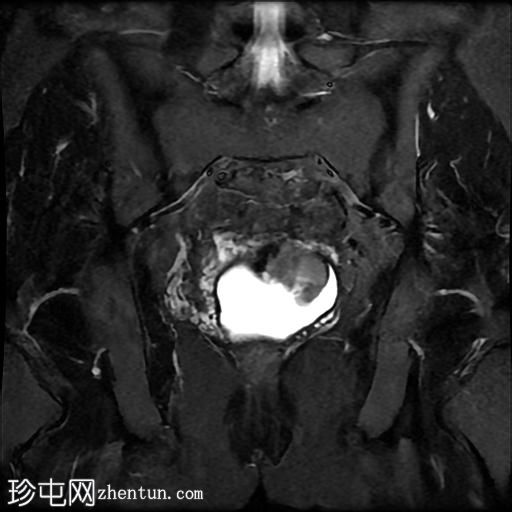

冠状位

T2加权像

该宫颈癌体积较大,局部晚期,大小为22 x 40 x 42 mm,起源于宫颈左后外侧壁,向下延伸至阴道上三分之一处,位于宫颈中后外侧壁。

病变还累及左侧前外侧的宫旁组织。

左侧髂内静脉分叉下方可见一异常信号淋巴结肿大,最大短轴直径(SAD)为 8 mm。该淋巴结在弥散加权成像(DWI)上显示水限制,并有对比增强。

影像学检查结果提示,根据 FIGO 分期系统,该患者为宫颈癌 IIIC1 期。

宫颈肿块活检的组织病理学报告显示为宫颈鳞状细胞癌,具体来说是角化型。